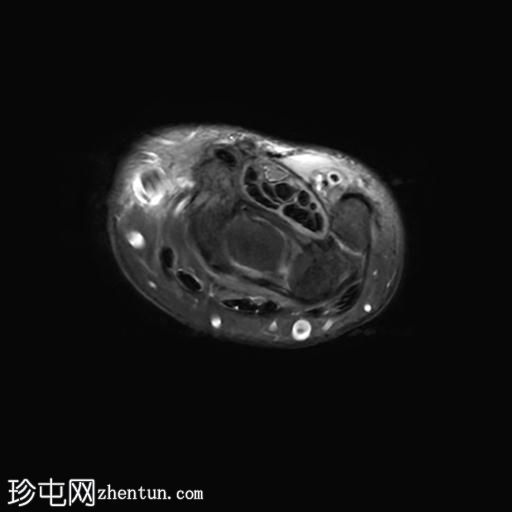

轴向PD值

脂肪饱和度

MRI显示腕部第一背侧肌腱(拇长展肌和拇短伸肌)增厚,并伴有异常增厚的实质内液体信号。腱鞘内液体增多。

尺侧腕伸肌腱可见异常线性实质内液体信号增多,与板状间质撕裂相关。